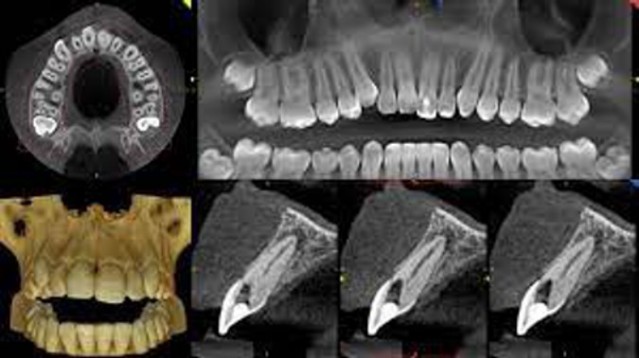

TAC (CBCT 3D)

per lo studio radiologico tridimensionale e morfometrico dell’anatomia del paziente utilizzando dosi di radiazioni minori rispetto alle TAC tradizionali (vedi radiologia 3D